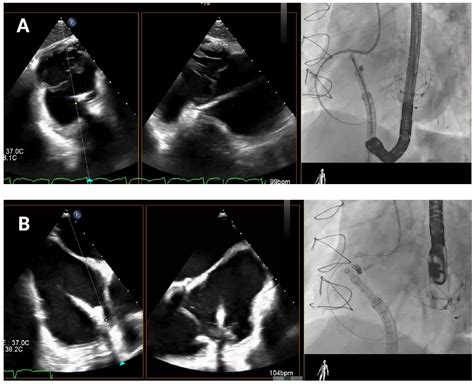

Transcatheter Tricuspid Valve Annuloplasty with the Cardioband System ...

mdpi.com